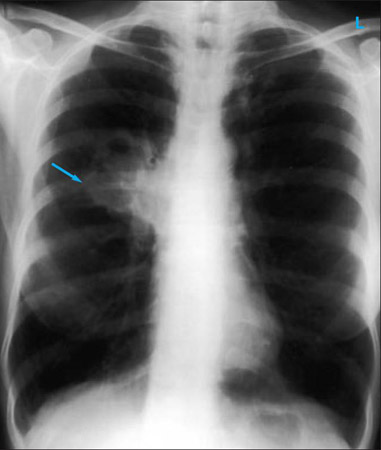

Chest x-ray

A chest x-ray should be obtained early in the evaluation of chronic cough.[38] Although it is not diagnostic of the most common causes, findings may quickly divert the evaluation to causes of greater gravity, such as structural lung diseases. These include lung cancer, pulmonary fibrosis, tuberculosis, bronchiectasis, pneumonia, aspiration, and sarcoidosis.[Figure caption and citation for the preceding image starts]: Chest x-ray showing hyperinflation in a patient with COPD. The hyperinflation is caused by the emphysema component of COPD, rather than the chronic bronchitis that underlies symptoms of coughFrom the personal collection of Dr M. A. Sharifabadand, SUNY at Stony Brook School of Medicine, Department of Pulmonary and Critical Care Medicine, Mineola, New York and Dr J. P. Parsons, The Ohio State University Medical Center, Columbus; used with permission [Citation ends].com.bmj.content.model.assessment.Caption@65a65855[Figure caption and citation for the preceding image starts]: Chest x-ray showing multiple miliary lung metastases (arrows). The primary tumour was a thyroid carcinomaE. Dick, Student BMJ. 2001;9:10-12 [Citation ends].com.bmj.content.model.assessment.Caption@25657fee[Figure caption and citation for the preceding image starts]: Chest x-ray showing left hilar carcinoma (arrow)From: E. Dick, Student BMJ. 2000;8:358-360 [Citation ends].com.bmj.content.model.assessment.Caption@567b9fef[Figure caption and citation for the preceding image starts]: Chest x-ray showing a cavitating right hilar carcinoma (arrow)E. Dick, Student BMJ. 2001;9:10-12 [Citation ends].com.bmj.content.model.assessment.Caption@3d6fa55[Figure caption and citation for the preceding image starts]: Chest x-ray in a patient with bronchogenic carcinoma showing a left-sided pleural effusionFrom: R. Thakkar, Student BMJ. 2001;9:458 [Citation ends].com.bmj.content.model.assessment.Caption@5b46acec[Figure caption and citation for the preceding image starts]: Chest x-ray showing interstitial fibrosis in a patient with amiodarone pulmonary toxicityFrom the personal collection of Dr A. Pataka and Professor P. Argyropoulou, Aristotle University, Thessaloniki, Greece; used with permission [Citation ends].com.bmj.content.model.assessment.Caption@2c3c94b0[Figure caption and citation for the preceding image starts]: Chest x-ray showing pulmonary tuberculosis with cavitationFrom the personal collection of Dr M. Narita, Department of Pulmonary and Critical Care Medicine, University of Washington [Citation ends].com.bmj.content.model.assessment.Caption@3dd7f84b[Figure caption and citation for the preceding image starts]: Chest x-ray showing multiple discrete nodules throughout both lungs (one of which is circled) in a patient with miliary tuberculosisE. Dick, Student BMJ. 2001;9:10-12 [Citation ends].com.bmj.content.model.assessment.Caption@23fa6365[Figure caption and citation for the preceding image starts]: Chest x-ray with lack of normal tapering producing a tram line in a patient with bronchiectasisFrom the personal collection of Dr S.M. Bhorade, University of Chicago Medical Center; used with permission [Citation ends].com.bmj.content.model.assessment.Caption@36b415f2[Figure caption and citation for the preceding image starts]: Chest x-ray with dilated and thickened airways in a patient with bronchiectasisFrom the personal collection of Dr S.M. Bhorade, University of Chicago Medical Center; used with permission [Citation ends].com.bmj.content.model.assessment.Caption@78e208fa[Figure caption and citation for the preceding image starts]: Chest x-ray showing increased opacification of the right perihilar region and superior segment of the right lower and upper lobes consistent with worsening aspiration pneumoniaFrom the personal collection of Dr R. Kanner, University of Utah School of Medicine [Citation ends].com.bmj.content.model.assessment.Caption@71be2c1f[Figure caption and citation for the preceding image starts]: Portable chest x-ray with bibasilar opacities, worse on the right than the left, in a patient with hospital-acquired pneumoniaFrom the personal collection of Dr F. W. Arnold, Division of Infectious Diseases, Department of Medicine, University of Louisville School of Medicine [Citation ends].com.bmj.content.model.assessment.Caption@2c704497[Figure caption and citation for the preceding image starts]: Chest x-ray showing early ill-defined opacities of the right upper lobe above the minor fissure consistent with early changes of aspiration pneumoniaFrom the personal collection of Dr R. Kanner, University of Utah School of Medicine [Citation ends].com.bmj.content.model.assessment.Caption@23fa54d0[Figure caption and citation for the preceding image starts]: A. Portable upright chest x-ray before aspiration; B. Chest x-ray 1 hour after aspiration, showing bilateral diffuse alveolar infiltrates, worse at the bases on the right sideFrom the personal collection of Dr S. Murgu and Dr H. Colt, University of California at Irvine Medical Center [Citation ends].com.bmj.content.model.assessment.Caption@7860be3a[Figure caption and citation for the preceding image starts]: Chest x-ray showing bilateral hilar adenopathy in a patient with sarcoidosisFrom the personal collection of Dr M.P. Muthiah, Division of Pulmonary and Critical Care and Sleep Medicine, University of Tennessee [Citation ends].com.bmj.content.model.assessment.Caption@31e94b4e